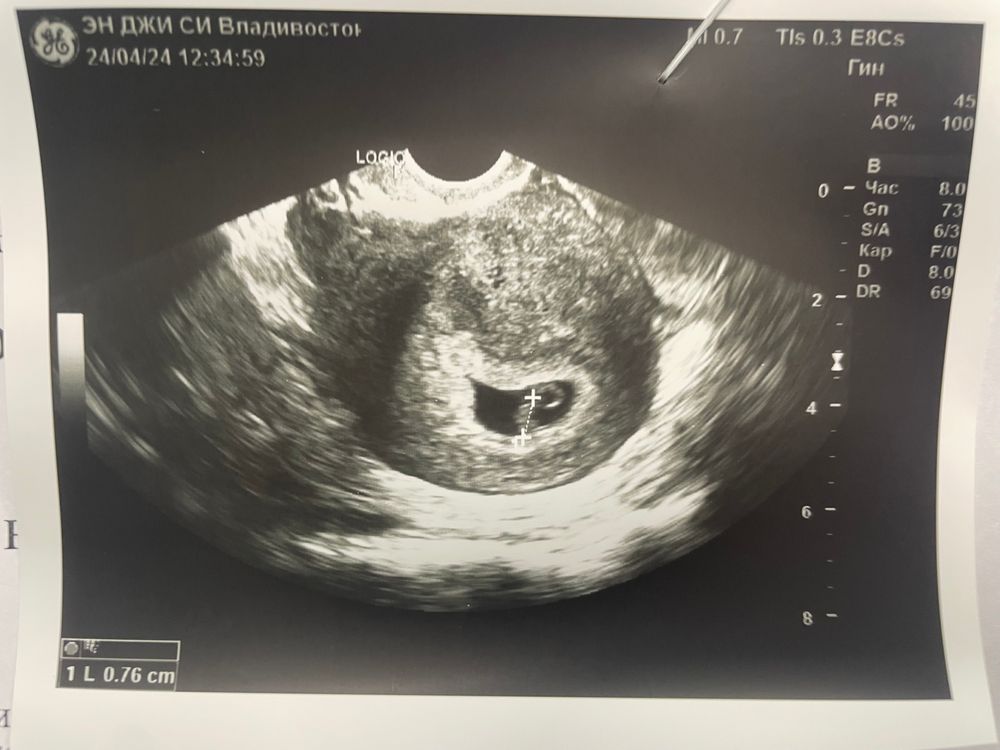

По результат узи ПЯ 22мм ЖМ 4,5мм КТР 7мм СБ+ и эмбрион четко визуализируется, срок 6нед+4дн (почему то в протоколе осмотра пишет срок со дня переноса) ну да ладно.